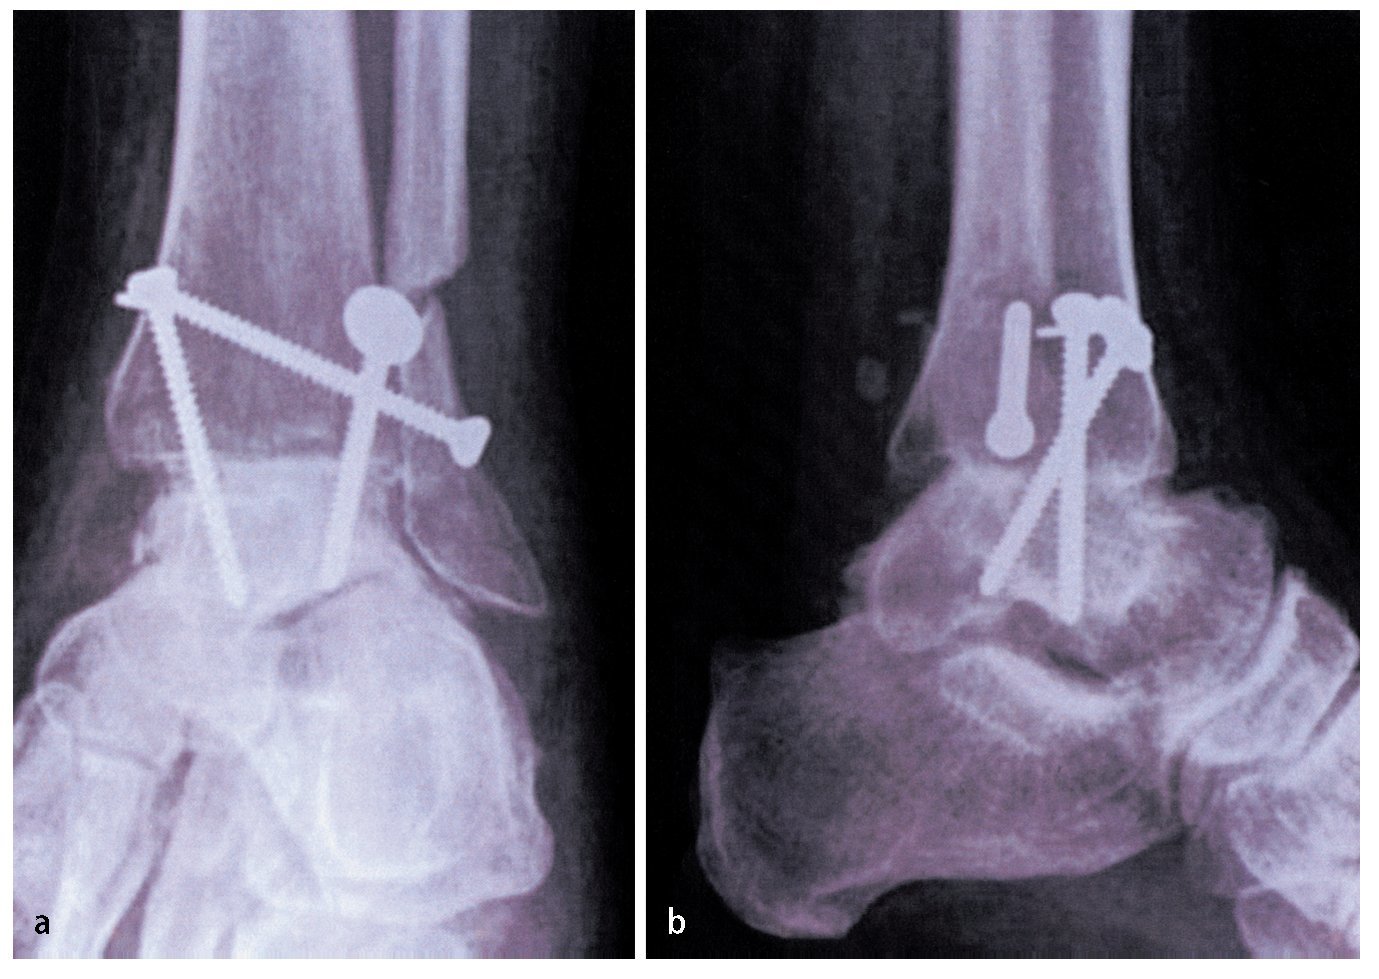

Fig. 13 Obtener radiografía anteroposterior y lateral intraoperatoria para comprobar la posición de los tornillos. Lavado y cierre de la herida con suturas absorbibles interrumpidas y con suturas no absorbibles para la piel. Vendaje compresivo estéril y férula por debajo de la rodilla. No se emplea drenaje de aspiración.

— Se debe evitar la colocación inadecuada de tornillos en otra posición que no sea un ángulo de 30 ° con el eje tibial. El punto de cruce debe ser proximal al pilón tibial ya que esto aumenta la estabilidad (fig. 13). Una posición inadecuada de los tornillos da lugar a más micromovimientos y, en consecuencia pone en riesgo la solidez de la fusión33.

Creemos que la construcción con 3 tornillos es biomecánicamente deseable cuando se utiliza una técnica de preparación de superficie con corte plano. Los tornillos colocados en paralelo producen mayores fuerzas de compresión. Sin embargo, puesto que se utilizan pinzas Weber para la compresión, nuestro objetivo es la construcción de tornillo más rígida. El uso de tornillos que se cruzan justo proximales a la superficie de fusión a un ángulo de 30º respecto al eje tibial ha demostrado ser superior para este fin10,15,33. Por lo tanto, la técnica descrita proporciona resultados fiables en seguimiento a largo plazo para una amplia gama de indicaciones de la artrodesis.